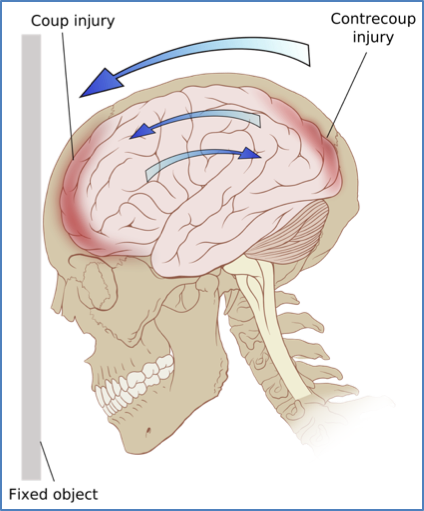

- Cause: High-force trauma (coup or contre-coup injury)

- Mechanism: Local bruising and swelling of brain parenchyma